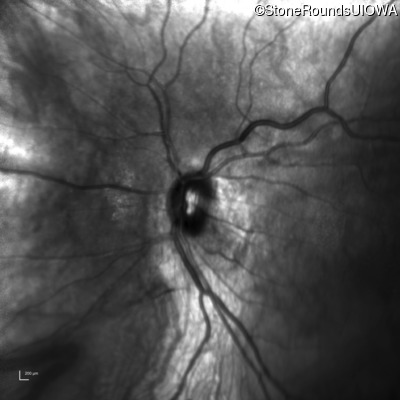

Age at visit: 41 years (Visit 2)

OD OS

This 41 year old woman was highly myopic as a child and experienced a rhegmatogenous retinal detachment OS at age 20.

The clinical features favoring the diagnosis of Sticker syndrome in this patient include extensive radial lattice degeneration, a personal and family history of rhegmatogenous retinal detachment, a history of cataract surgery before age 30 (and very high myopia before that), arthritis in her knees and hips and a slightly flattened mid-face.